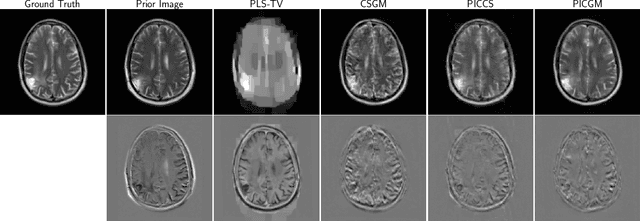

Obtaining an accurate and reliable estimate of an object from highly incomplete imaging measurements remains a holy grail of imaging science. Deep learning methods have shown promise in learning object priors or constraints to improve the conditioning of an ill-posed imaging inverse problem. In this study, a framework for estimating an object of interest that is semantically related to a known prior image, is proposed. An optimization problem is formulated in the disentangled latent space of a style-based generative model, and semantically meaningful constraints are imposed using the disentangled latent representation of the prior image. Stable recovery from incomplete measurements with the help of a prior image is theoretically analyzed. Numerical experiments demonstrating the superior performance of our approach as compared to related methods are presented.